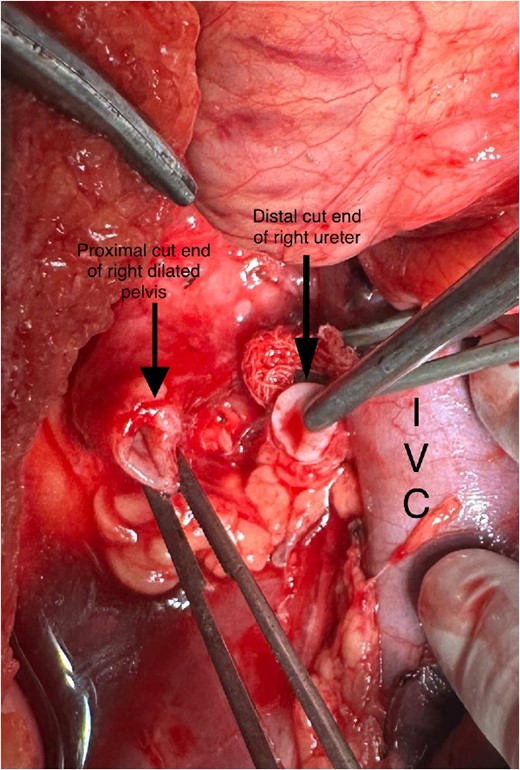

A midline incision was given, and the abdomen was opened from 4 cm below the xiphisternum to 3 cm above the pubic symphysis. The ascending colon along with the hepatic flexure was completely mobilized medially to expose the retroperitoneum. Careful dissection was done to identify the IVC and its the relations to the right ureter. The proximal dilated ureter and right pelvicalyceal system were identified, and dissection was continued laterally. The ureter was traced and noticed to course behind the IVC at the level of the L2–L3 vertebra, exiting to lie medially in the groove between the IVC and the aorta (Fig. 3). The ureter was divided proximal to the point where it coursed behind the IVC until it came out medial to IVC (Fig. 4). The retrocaval segment was brought anteriorly, resected from the normal distal ureter, and ureteropelvic anastomosis was done using 3–0 Polyglactin sutures lateral to the IVC (Fig. 5). This procedure eliminated the compression on the ureter. An abdominal drain was placed.

Intraoperative image showing pelviureteric anastomosis after resection of retrocaval part of the ureteric segment.